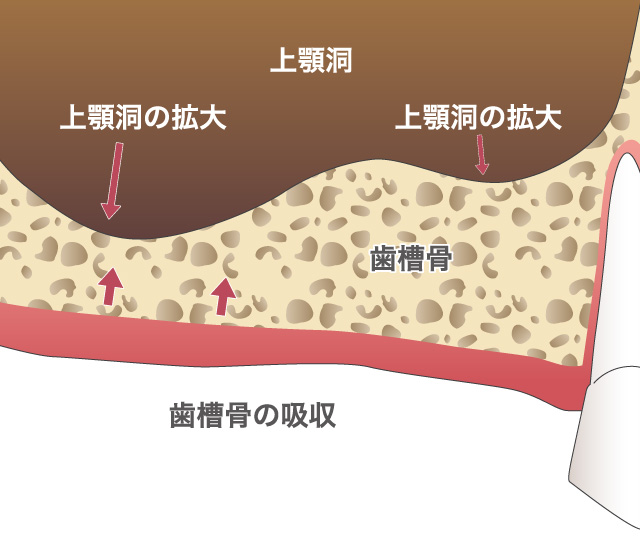

一度歯を失ってしまうと、天然の歯は二度と元に戻ることはありません。その失われた歯が引き金になり、隣の歯がドミノ倒し的に悪化してしまう可能性もあります。しかし、インプラント治療を行うことで、自分の歯とほとんど変わらない見た目や、噛み心地を得ることが出来ます。ご自身の健康な歯を守ることができます。

インプラント治療とは術前診査・診断を十分に行った上で、歯が抜けてしまった部分にインプラント(人工歯根)を埋め込み、その上から自然な見た目の人工歯を装着させるという治療法で、骨にしっかりとインプラント(人工歯)を定着させるため、自分の歯のようにしっかり、思い切り噛めるようになります。